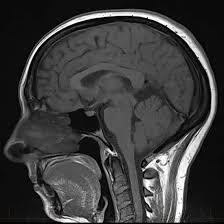

MRI head scanning provided by Medifyhome is a non-invasive overall check-up procedure for the brain and its surrounding structures. Advanced imaging technology allows the detection of tumors, strokes, and other neurological disorders with the utmost precision. The procedure takes about 30 minutes to 1 hour and does not require any radiation as well. So, it is completely safe for assessing the brain. Patients are guided throughout the entire experience with full explanations beforehand.